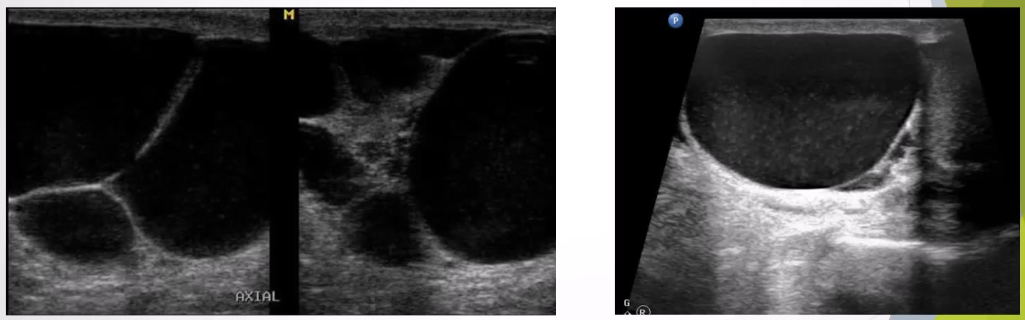

Varicocele: Dilatation of the pampiniform plexus of veins within the spermatic cord and the most common mass of the spermatic cord. Most common cause of male infertility

Ultrasound Appearance:

Dilated veins >2-3 mm in diameter

Scrotal mass with a "Bag of worms" appearance above or posterior to the testes

Veins increase in size with Valsalva maneuver.